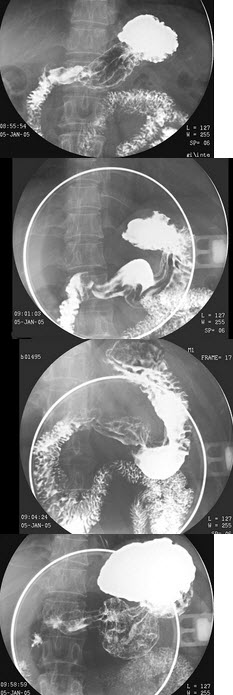

8、多项选择题 胰头癌低张十二指肠造影的X线征象为()

A.十二指肠曲扩大

B.十二指肠曲缩小

C.十二指肠内缘呈反“3”字征

D.十二指肠内缘双边征

E.十二指肠内侧呈锯齿状